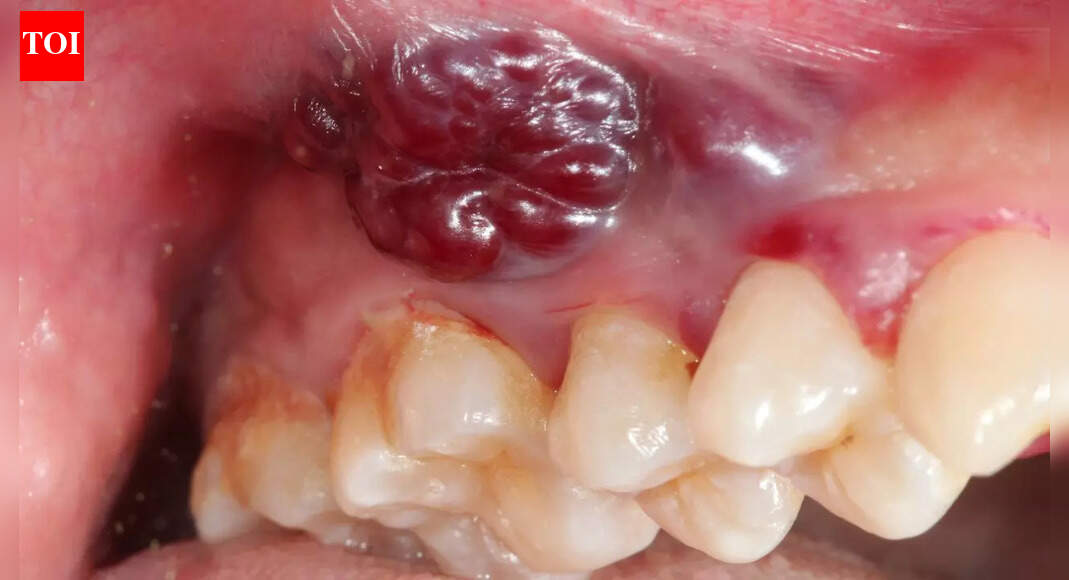

A mouth ulcer is usually seen as a small irritation that appears after accidentally biting the inside of your cheek or eating spicy food when the body is stressed. Most people expect it to heal on its own within a few days and rarely think twice about it. However, for an increasing number of Indian women, a simple ulcer that refuses to disappear is becoming an early sign of something far more serious. Oral cancer is rising across urban India, and one of the earliest visible warnings is a non-healing ulcer inside the mouth or on the lips. Paying attention early can genuinely save lives and prevent late-stage diagnosis. A peer-reviewed study published in the Journal of Oral Biology and Craniofacial Research found that persistent ulcers and white or red patches were common early indicato

Indian women and growing oral cancer cases: Why a non-healing mouth ulcer could be the earliest red flag